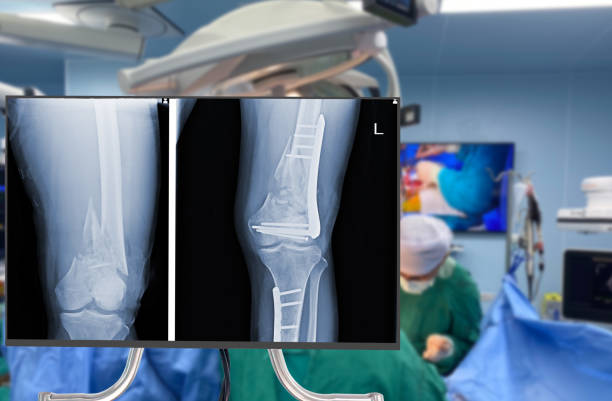

An orthopedic surgeon specializes in disorders and diseases of the musculoskeletal system. He or she uses both non-operative and surgical techniques to reduce pain, heal fractures and strains, correct joint deformities, improve range of motion and ambulation, and more.

Regarding joint replacement procedures, the right surgeon is board-certified and fellowship-trained in joint arthroscopy and arthroplasty. The physician also has a long track record of medical practice, including the exact procedure to bring your joint back to full function and health.